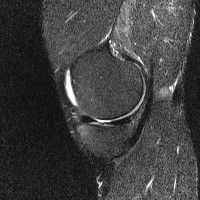

무릎 mri 간단히 봐주실 수 있으시나요 ㅠㅠ

안녕하세요 8년전 십자인대 수술하고 최근 무리한 운동에 무릎 불편감이 생겨서

mri 찍었습니다.

진단결과는 첫 찍은 병원에서 활액막염 이라는 진단을 받았습니다. 혹시 봐주실 수 있으실까요?

올라온 MRI가 단편적이라서 정확한 진단에 어려움이 있지만 십자인대에는 큰 이상이 있지는 않은것 같으며, 무릎관절내 물이 있는 것으로 보아 활액막염의 진단이 맞을 것 같습니다.

하지만 단편적인 영상이기 때문에 촬영병원에서 정확한 판독지 등을 받으시는 것이 좋겠습니다.